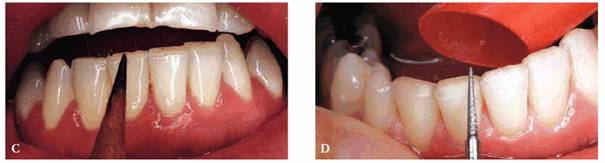

Figure 17-9A shows a 29-year-old female who has

abrasion and gingival recession confined to the anterior left segment,

involving the canine and two incisors on that side. Closer examination revealed

the smooth, rounded nature of the abraded areas (Figure 17-9B). Although she could not recall her

specific age at the time, she reported that she was told by a hygienist that

her brushing technique was improper when she was a teenager. She stated that

she was instructed in brushing and flossing by this hygienist and had noted no

progression of the recession since that time. For the past 8 years, she has

been a patient in the same dental practice, and the clinical charting indicates

that there has been no worsening of the problem. She has been informed about

gingival surgery to correct the defects but has declined since she does not

show her teeth when smiling.

Figure 17-9A: A 29-year-old female with abrasion confined to the maxillary left canine and lateral and central incisors.

Figure 17-9B: Close examination reveals smooth, rounded, abraded areas that are suspected to be the result of improper brushing.